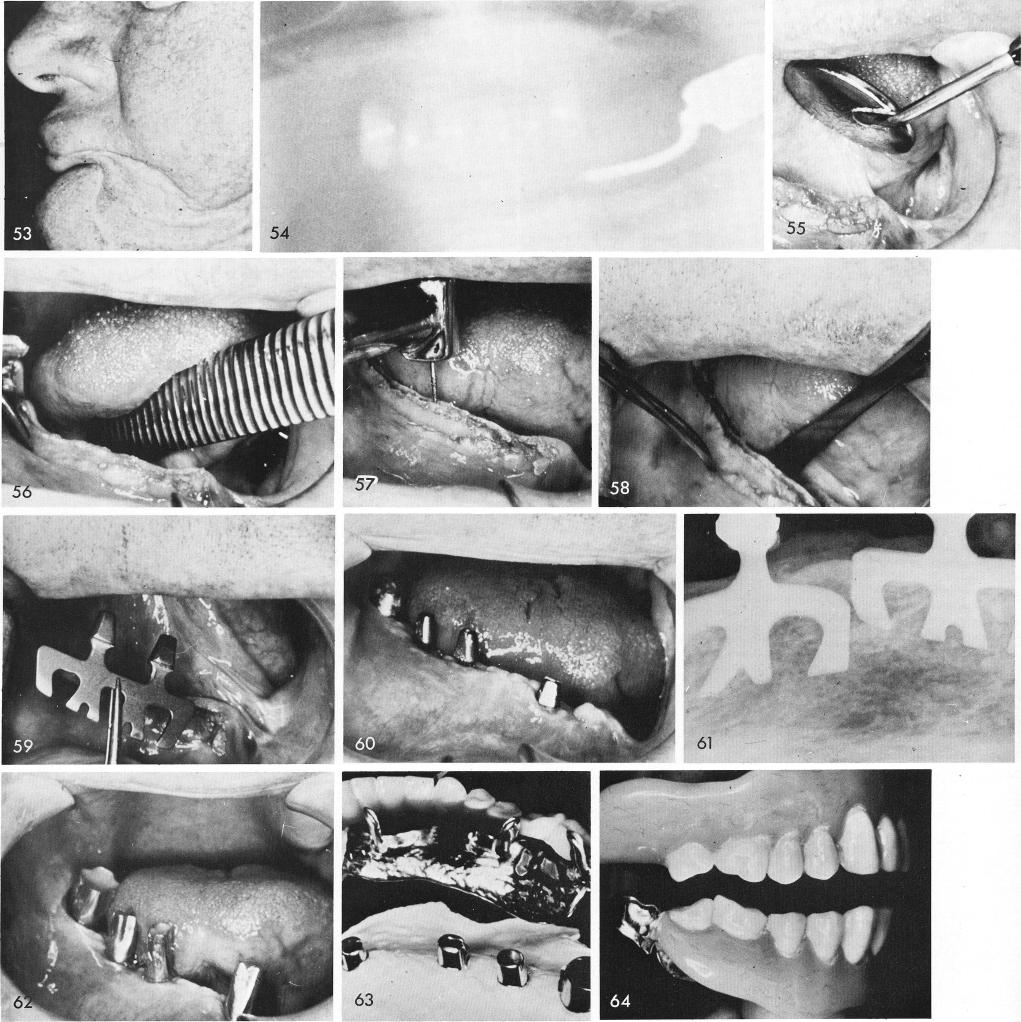

A patient with the entire left body and ramus of the mandible removed was helped considerably for several years before he deceased, fig. 53. A single molar tooth remained on his right side, fig. 54. The tissue was incised and reflected, figs. 55, 56, and a long groove was made along the entire length of the remaining half of the mandible, figs. 57, 58. Blades were carefully placed into the deepened socket, fig. 59. The tissues healed remarkably well, fig. 60. Notice the gold telescopic coping over the remaining molar tooth. Fig. 61 shows a periapical film revealing both blades. Copper bands festooned, shaped and filled with rubber material, fig. 62, were used in con-junction with a full arch rubber impression inside a tray to facilitate the laboratory procedures